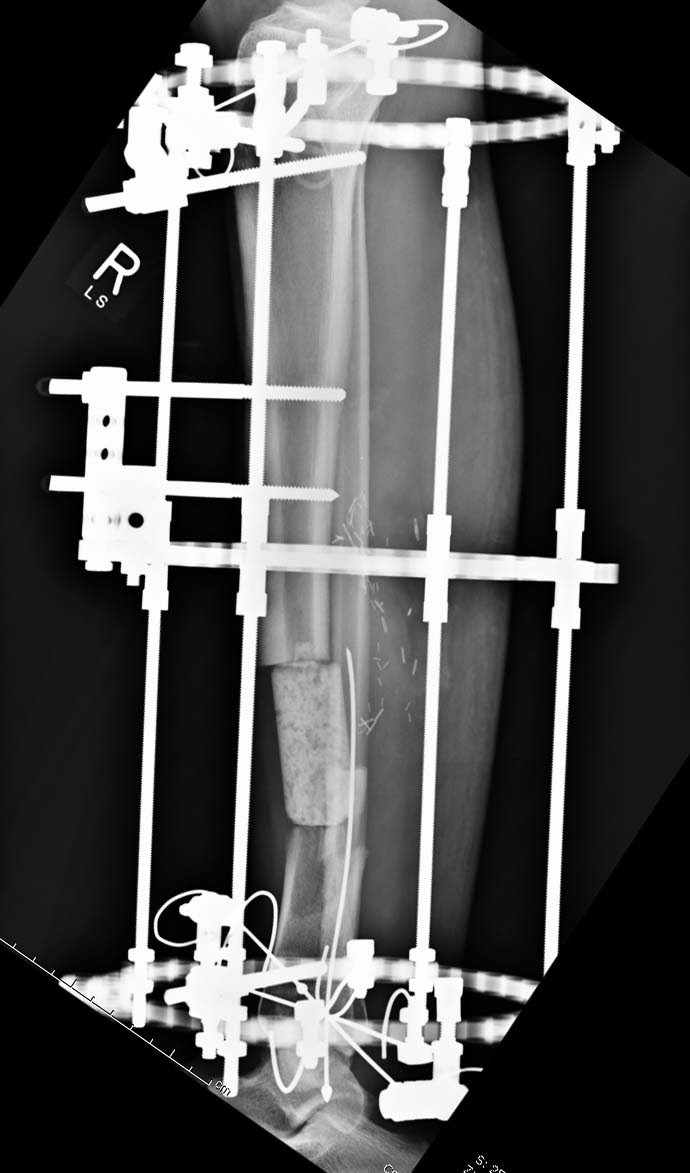

Данный случай не огнестрельная рана, а результат мотоциклетной аварии.

Независимо от повреждения при таких обширных дефектах мягких и костной

тканей применяется схожая тактика. Как видно, после нескольких I&D для

создания “pseudo membrane” применили цилиндрический блок из цемента.

Дефект мягких тканей закрыли свободным Anterior Thigh Graft. Из малого

доступа цилиндр удален небольшими кусочками, а пространство заполнили

бусами для освобождения пространства. По мере приближения регенерата

освободили пространство удалением бус через небольшой разрез. Этап

созревание регенерата можно было ускорить усилением интрамедуллярным

гвоздем, но решили закончить методом Илизарова.